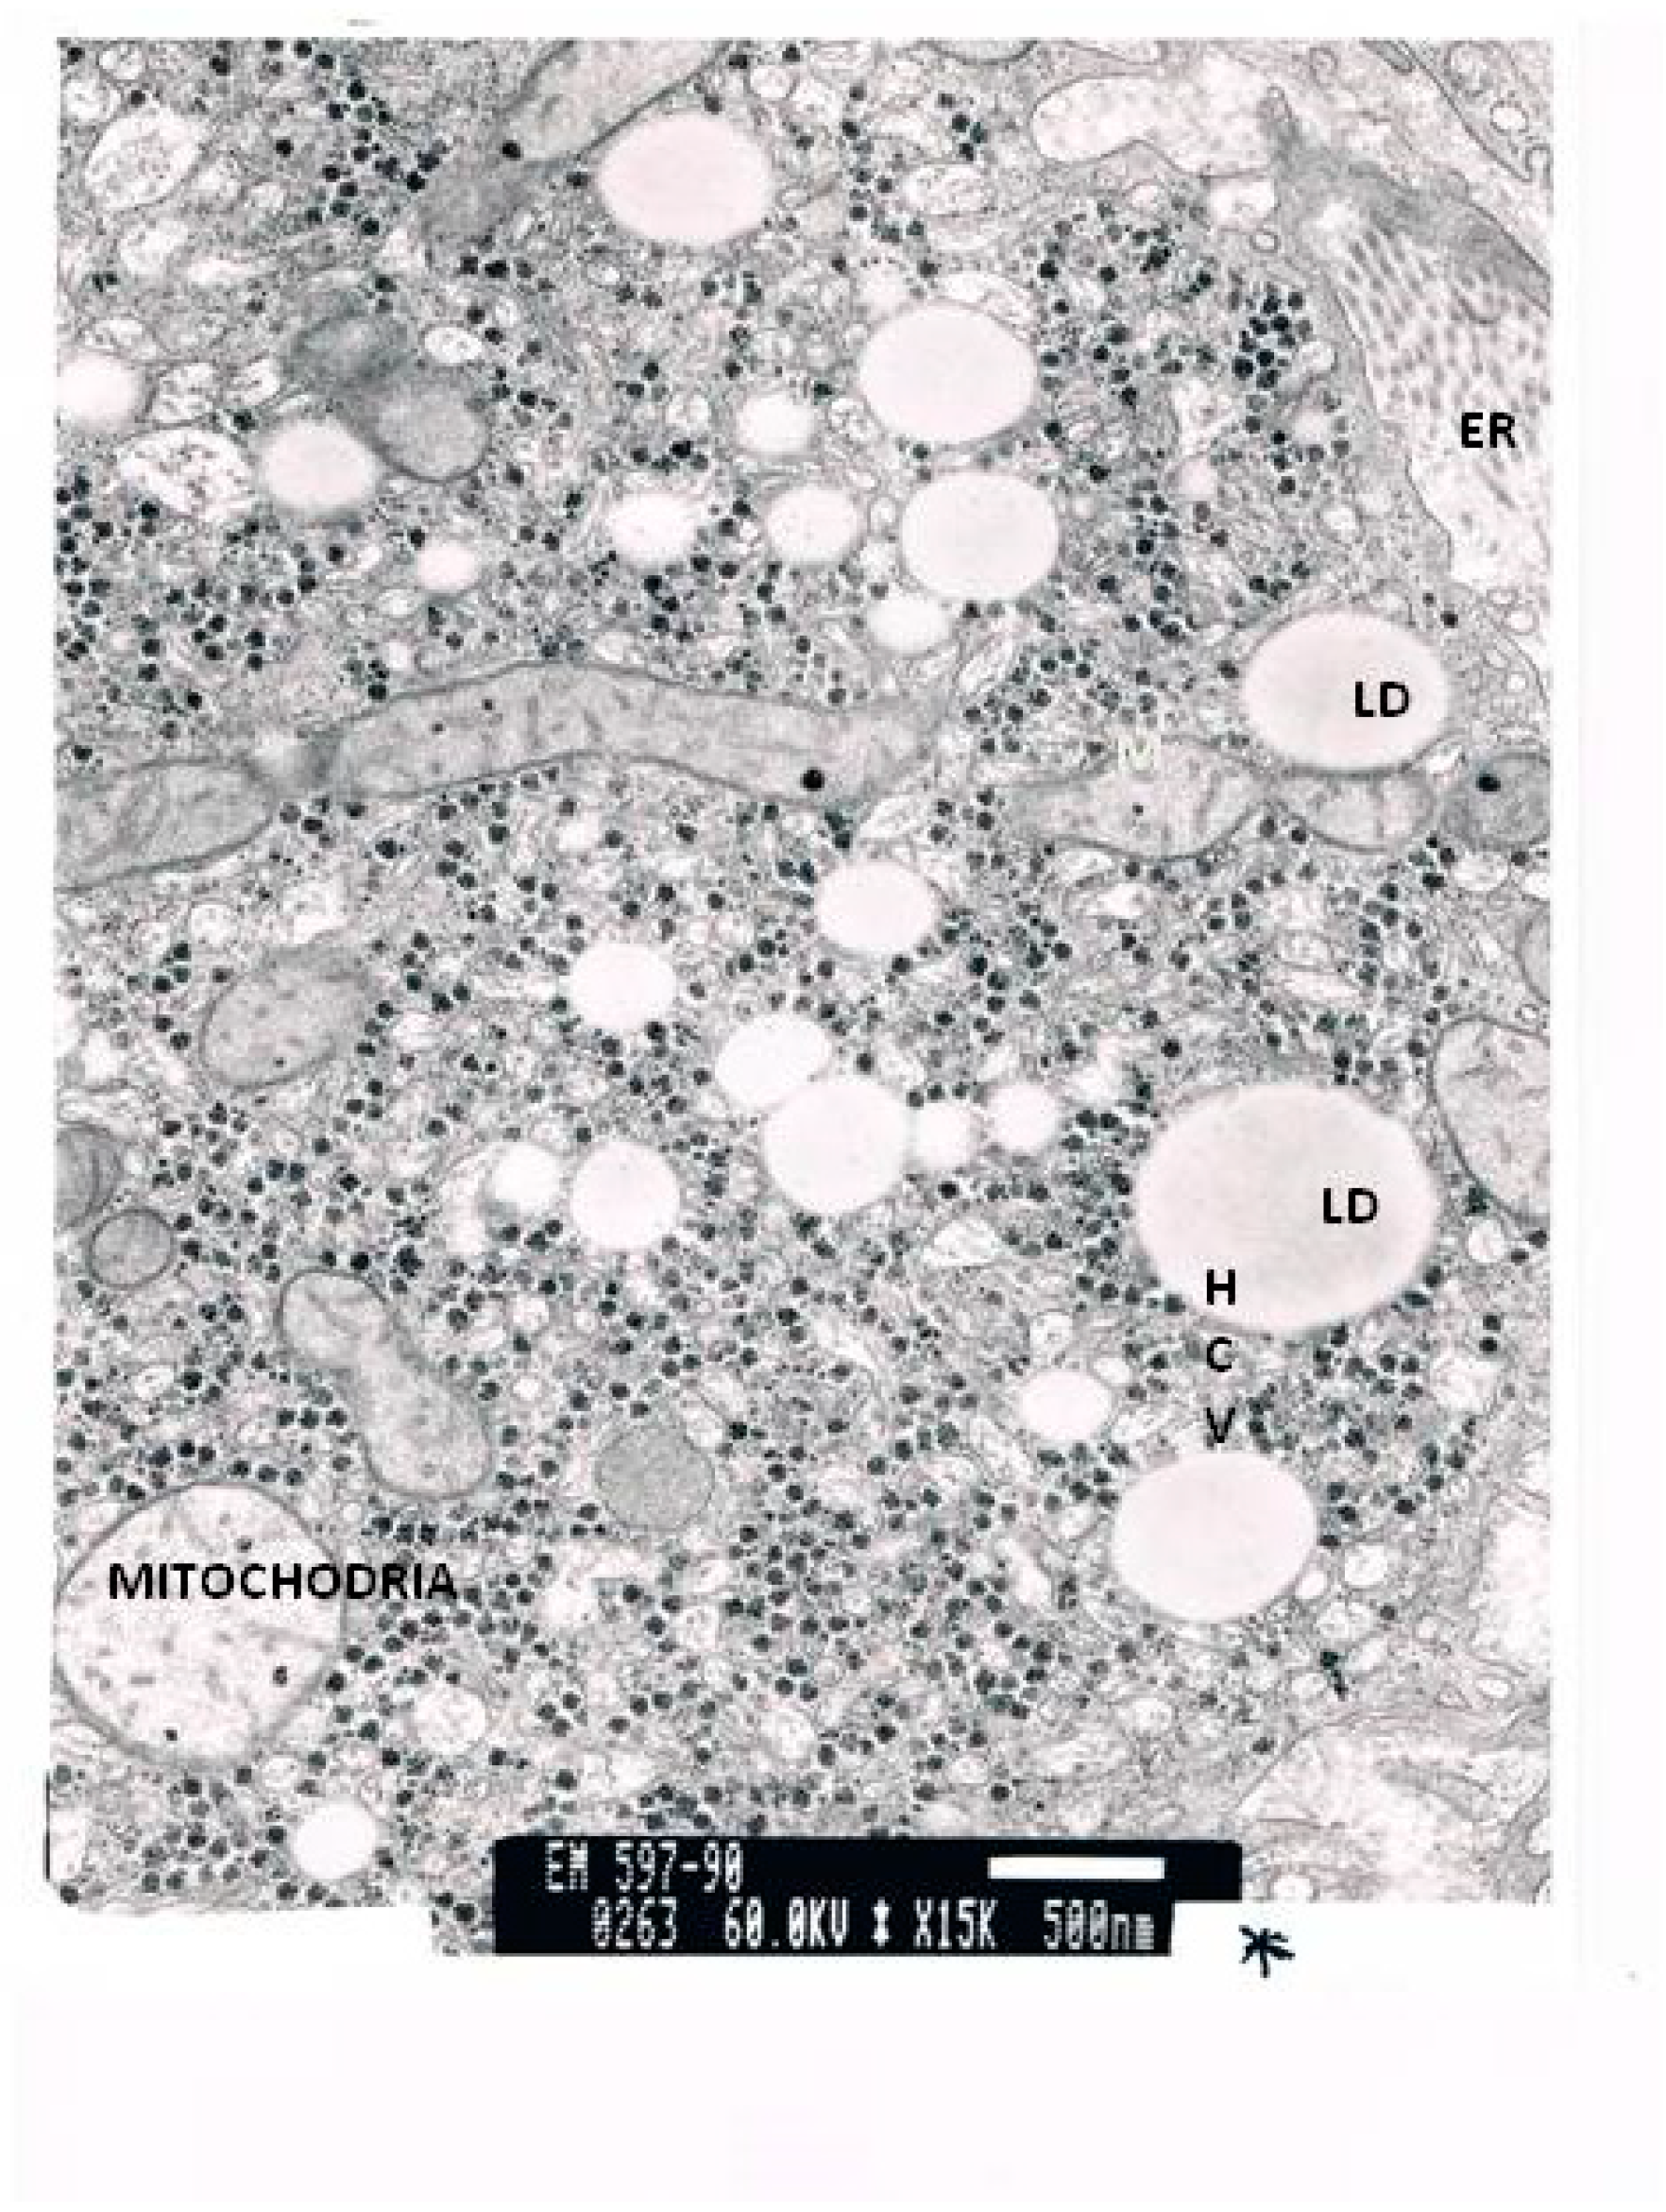

The TEM micrographs present several apoptotic hepatocytes and apoptotic bodies (AB). The micrographs show large deposits of lipids in the cell. The micrograph reveals an enlarged smooth endoplasmic reticulum (ER) and numerous mitochondria. While some mitochondria are normal, others have lost their cristae. An HCV antigen can be observed. In addition, the relative number of stellate cells per 100 hepatocytes was more than ten times higher than in the controls. The number of lipid vesicles stored in these stellate cells was 20 times higher than in the controls. Stellate cells in a normal liver only carry between one and four lipid vesicles.

Figure 3.

TEM of a liver biopsy. Many giant lipid vesicles and large confluent lipid droplets can be observed. There are many enlarged mitochondria with scattered unregular cristae. HCV antigen can be observed. HCV antibodies are present.

Figure 4.

An electron micrograph of a liver biopsy of a patient, which shows hepatocytes containing large lipid droplets, enlarged endoplasmic reticulum, mitochondria with few cristae and HCV antibodies.